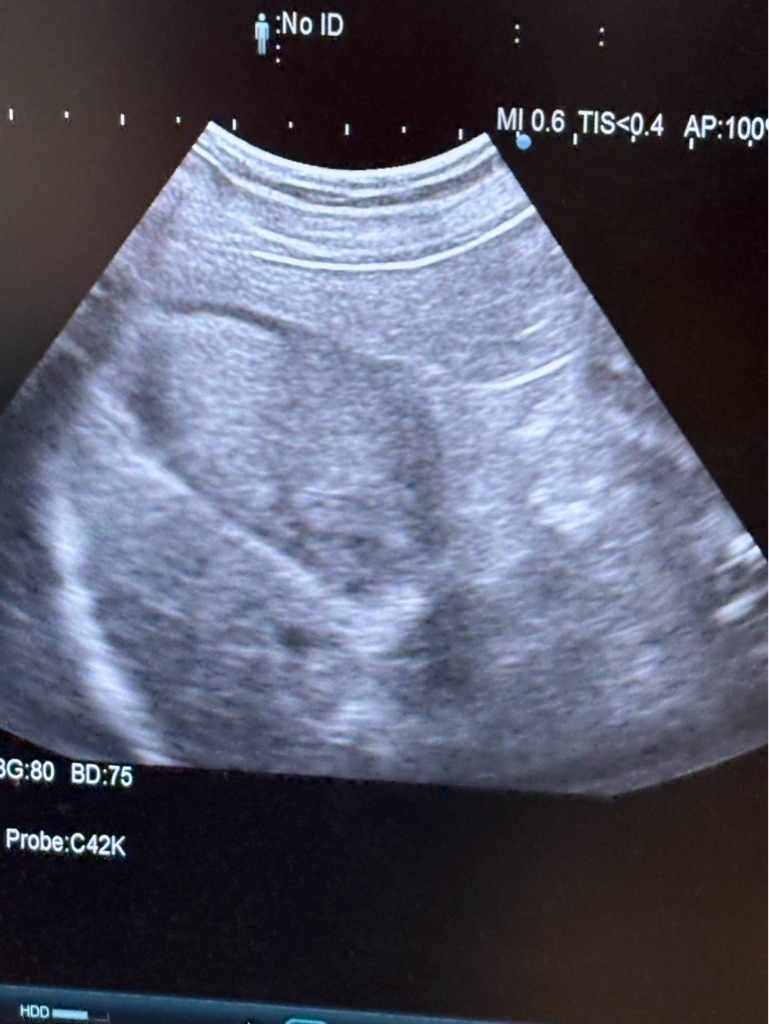

下のツグミちゃんも食欲がなくて

クリニックには診察に来ています。エコーで胆嚢に少し胆泥が溜まっているそうです。